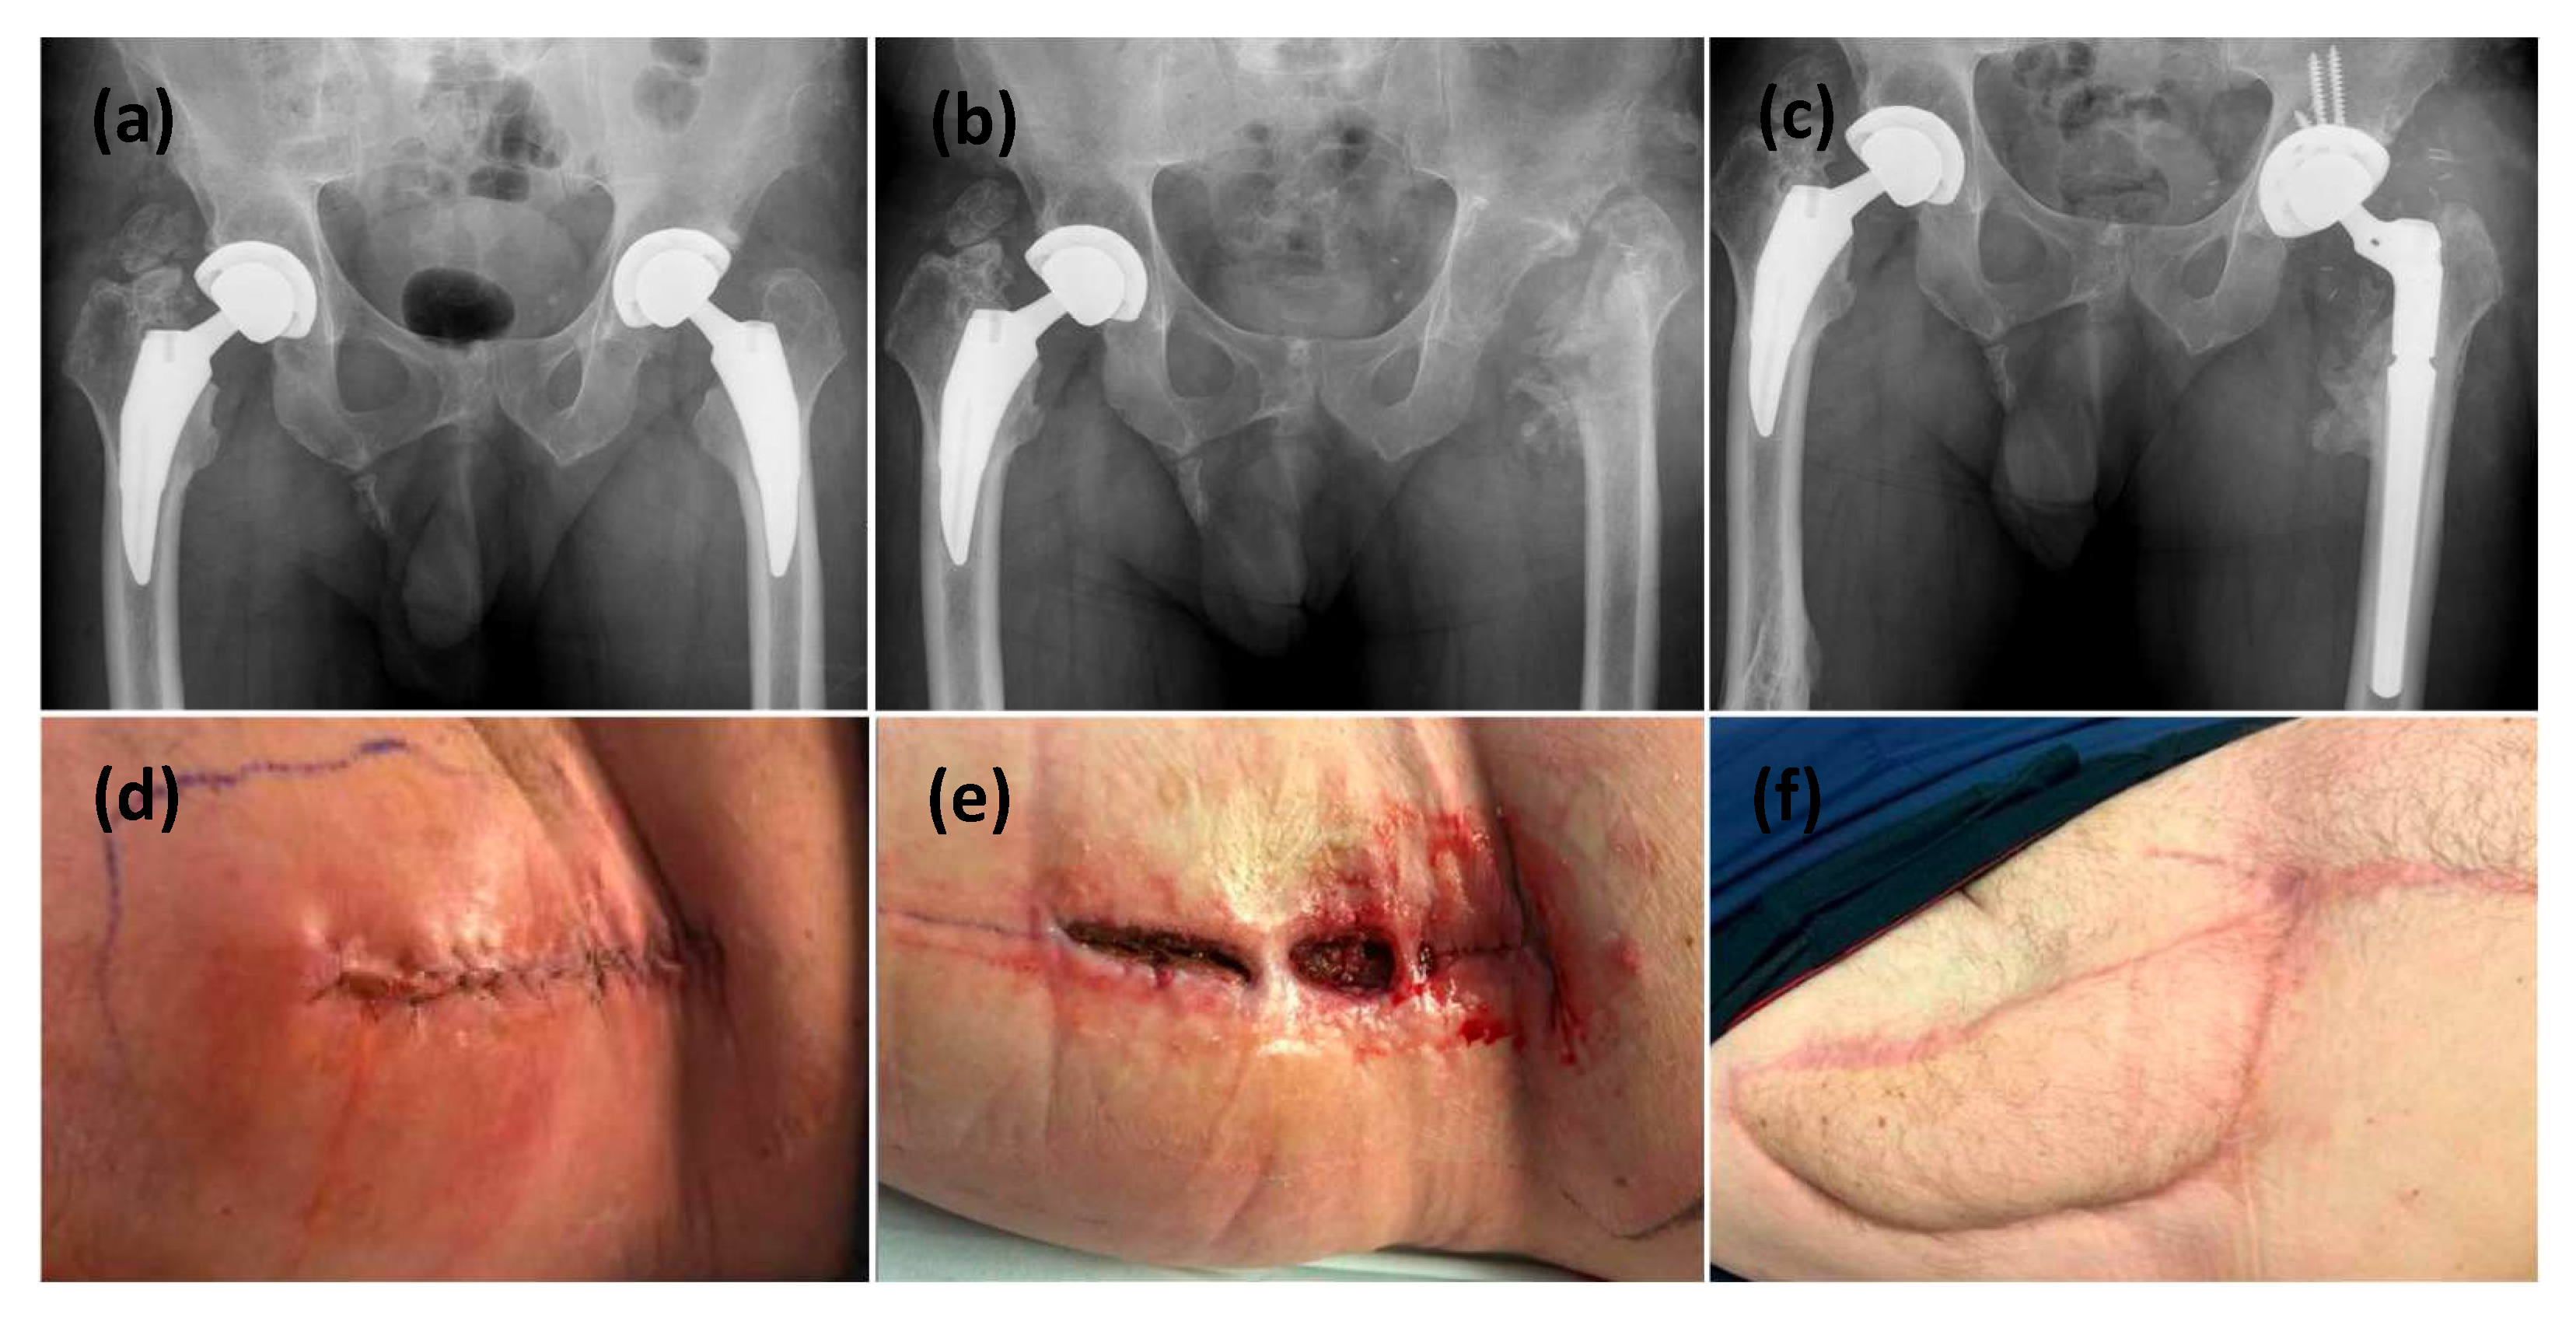

All patients had retained implants at final follow-up, either through initial implant retention or successful reimplantation (Table 3). Two patients had their implants removed prior to VRAM flap reconstruction as part of infection control (Figure 1). Following reconstruction, both achieved successful infection eradication and proceeded to prosthesis reimplantation. The remaining three patients retained their implants at the time of VRAM flap reconstruction and underwent extensive debridement with modular component exchange (Figure 2). Of these, one achieved complete wound healing and infection control. The other two experienced persistent infection—one required flap elevation, five additional debridements, and a two-stage revision. Despite the prolonged course, infection was ultimately eradicated, and reimplantation was performed 2 years and 8 months later, with the flap remaining viable throughout. The second patient continued to have a draining sinus but retained the implant. A summary of procedures and outcomes is shown in Figure 3.

Figure 1. This is a figure of left hip PJI with all revisions performed through a direct anterior surgical approach. (a) Initial AP pelvis x-ray showing bilateral osteoarthritis necessitating bilateral uncemented total hip replacements. (d) clinical presentation with initial symptoms of PJI at 4 weeks post index surgery. (b) After 3 operations to control PJI, the patient ended up with a resection arthroplasty. (e) The hip incision failed to heal after 4 weeks. (f) a VRAM flap was used to reconstruct the anterior hip wound and a reimplantation for the prosthesis was performed through an anteriorapproach. (c) Final postoperative radiograph showing the definitive implant inserted after wound healing and infection controlled.